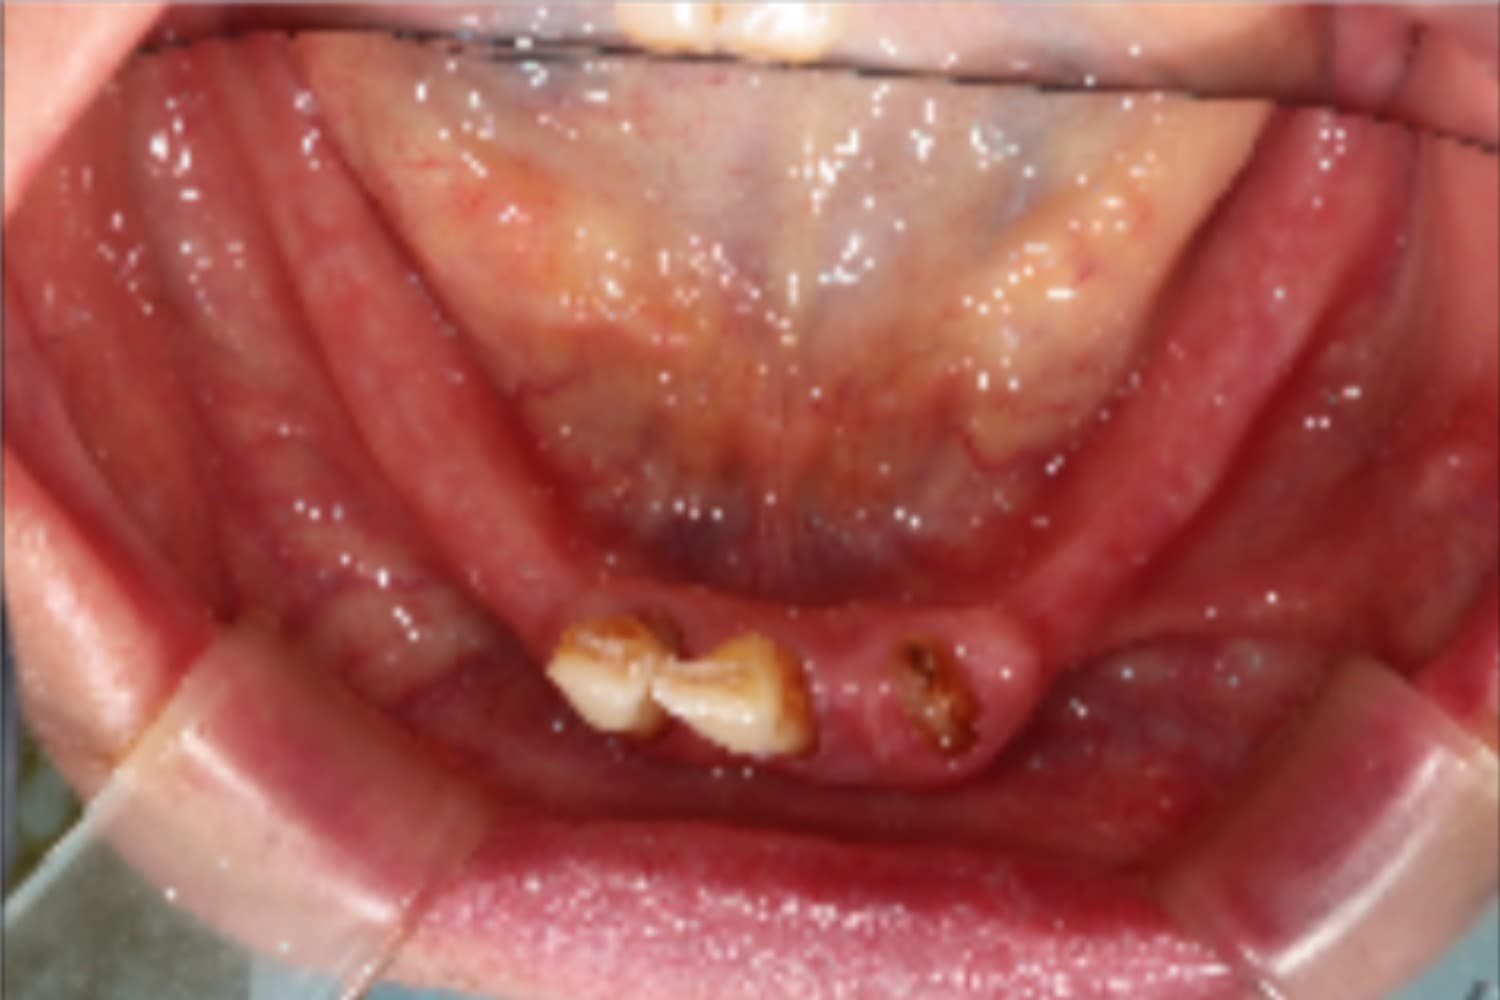

下顎すべてのインプラント治療

Before

After

下の前歯は抜歯と同時にインプラント4本を埋入し、その日に仮歯を装着してます(All-on-4)。

主訴

下の前歯がぐらぐらする

治療期間

6カ月

治療回数

12回

費用

3,080,000円

副作用・リスク

・インプラント埋入時の神経損傷リスクがあります。